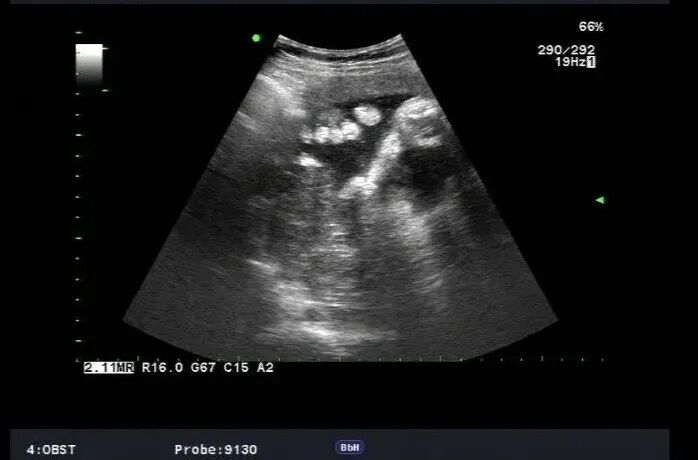

​咱们先来看个病例,孕妇30岁常规胎儿系统畸形筛查发现

手指横断面仅显示两个,指间隙明显增大,裂隙深